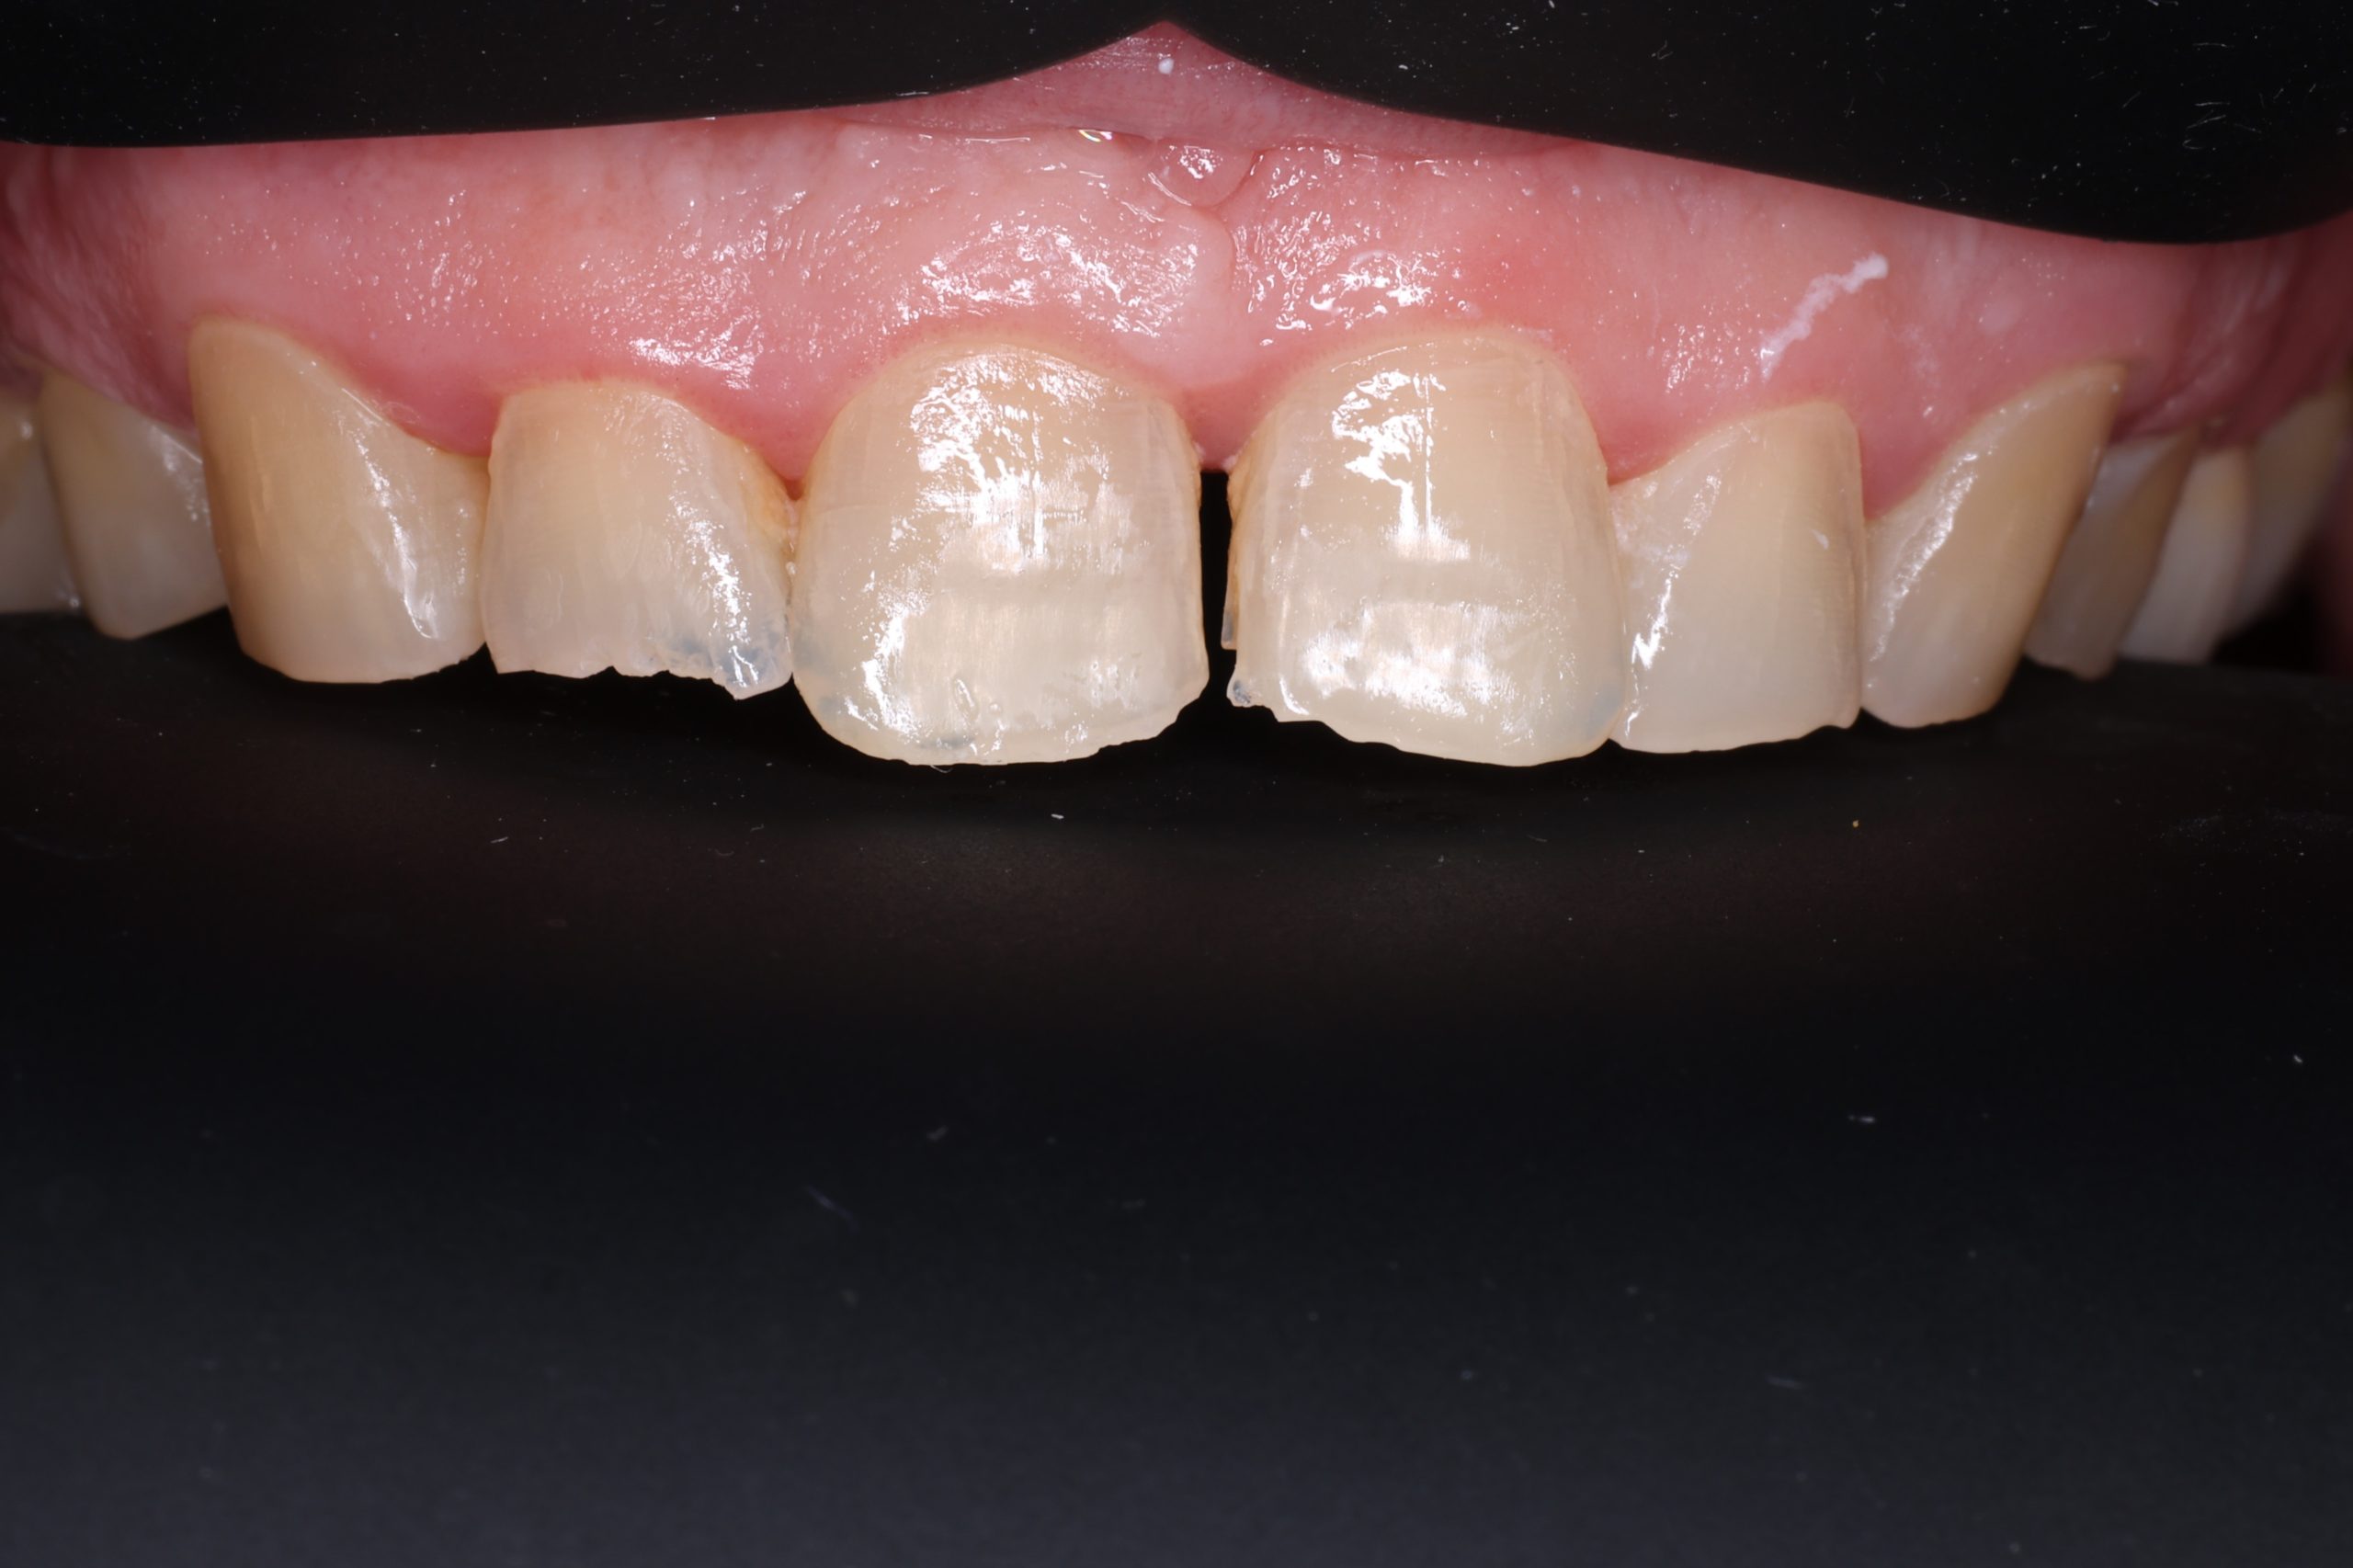

1. Preparation of the Tooth

We remove weakened or decayed tissue and clean the area thoroughly. The goal is to preserve as much healthy structure as possible.

3. Layering the Composite Resin

The tooth-coloured resin is applied in thin layers and shaped carefully to match natural anatomy. For front-tooth work, we may combine several shades for a lifelike result.